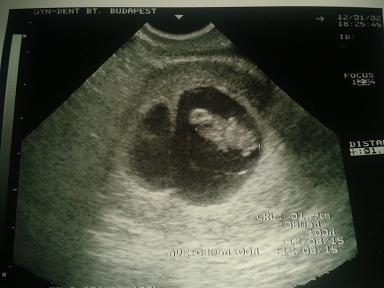

A hasam rohamosan nő :O Levinél ilyenkor még egyáltalán nem lehetett semmit látni, most meg... egyik anyuka ismerősömnek mutattam egy képet a hasamról, és visszakérdezett, hogy csak nem ikrek?!

Hát mondjuk nem bánnám

Minden álmom, hogy ikerlányaim legyenek

)) De majd nemsokára kiderül, hétfőn hívom a dokim, mert akkor jön vissza szabiról, és remélem már arra a hétre tud is adni időpontot, mert már nagyon izgulok

Kipróbáltam én is a kínai naptárat meg a gyűrűs módszert és mindkettő lányt mutatott